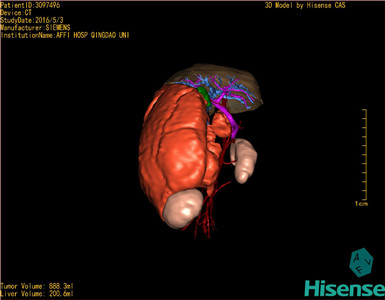

将0.625mm双源薄层CT资料的静脉期和动脉期Dicom格式文件导入海信CAS系统。

通过调节窗宽窗位调整CT序号,对肿瘤,肝实质,胆囊,下腔静脉,肿瘤,肝动脉、门静脉及肝静脉等进行三维重建;系统自动计算肿瘤体积和肝脏体积。(模拟手术操作,自动计算切除肿瘤体积。

术前三维重建:

重建图片